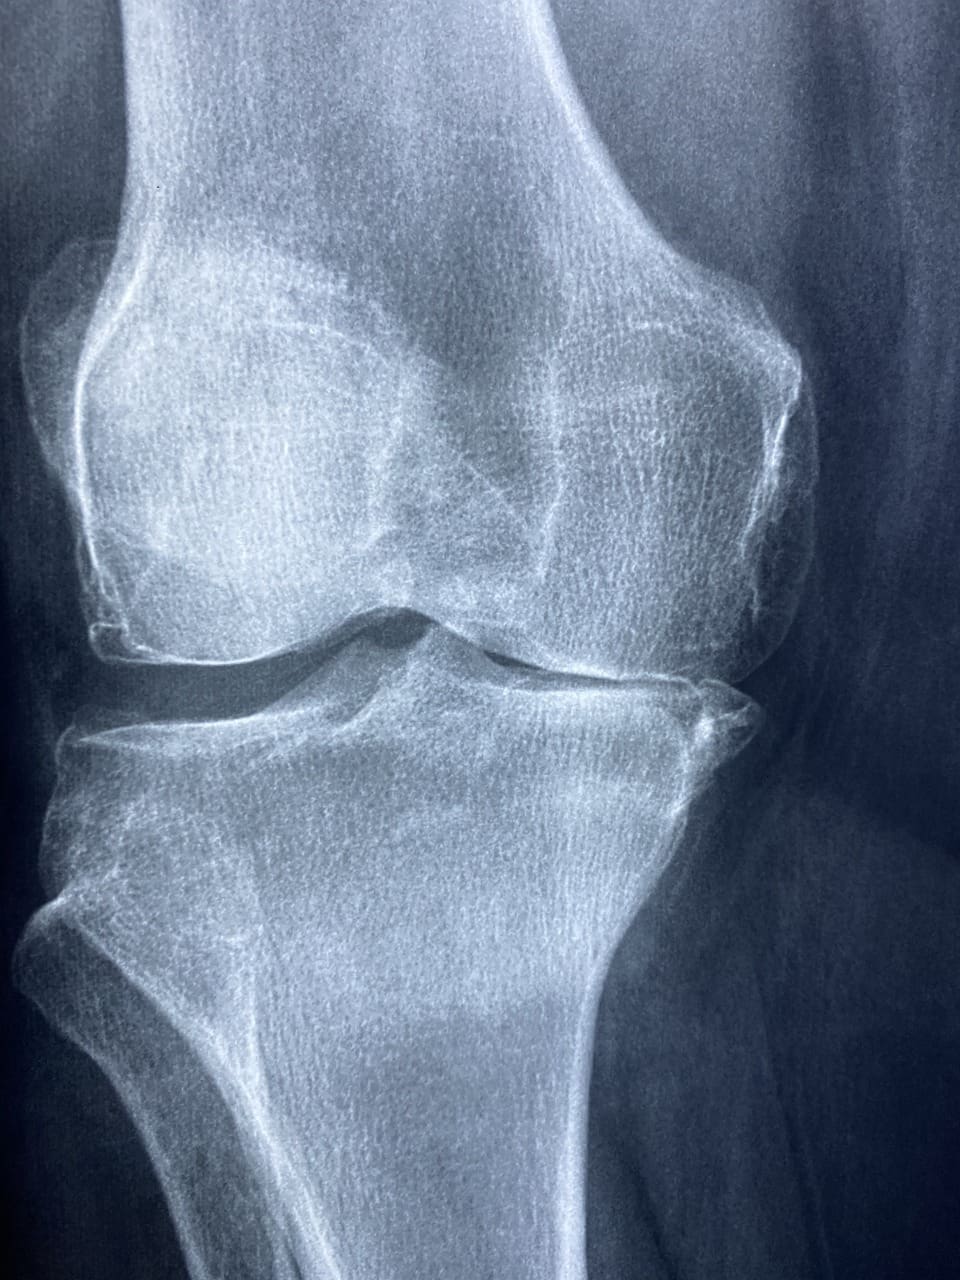

Before we dive into the ways you can support your loved one with rheumatoid arthritis, it’s important to have a basic understanding of the condition itself. Rheumatoid arthritis is an autoimmune disease that causes inflammation in the joints, leading to pain, swelling, stiffness, and decreased mobility. It can also affect other organs in the body, such as the heart, lungs, and skin.